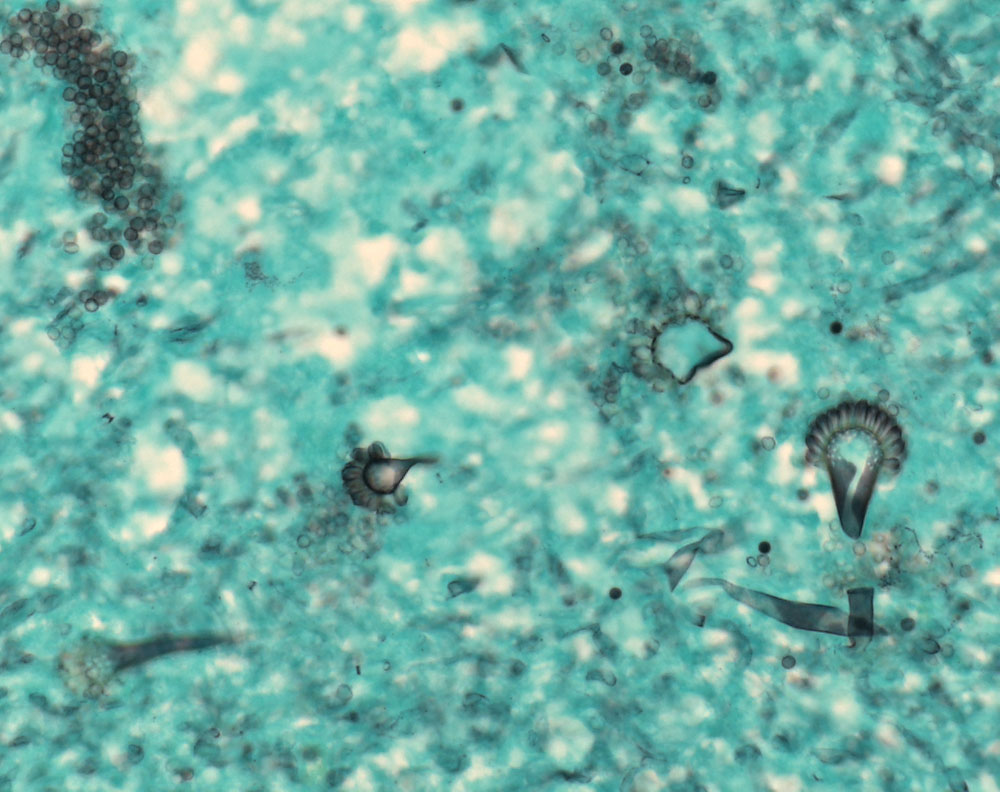

Aspergillen gehören in die Gruppe der Schimmelpilze und wachsen ubiquitär auf organischen Stoffen. Der Erreger ist charakterisiert durch echte septierte Hyphen von 3 bis 6 Mikrometer Durchmesser. Die Hyphen verzweigen sich in einem Winkel von 45 Grad. Fruchtköpfe (Conidiophoren) sind selten nachweisbar. Aspergillusinfekte manifestieren sich je nach Resistenzlage in folgenden Formen der fungalen Rhinosinusitis: